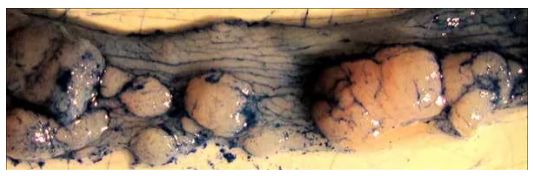

3. 處死后取小鼠結(jié)腸,可觀察形成的腫瘤。值得注意的是,末端結(jié)腸/直腸腫瘤負(fù)荷較高(左上圖),近端結(jié)腸腫瘤呈現(xiàn)褶皺狀紋理(右上圖),腫

瘤負(fù)荷很少。近距離觀察末端結(jié)腸可觀察到許多不同大小的腫瘤(下圖)。

4. 使用阿新藍(lán)染劑染色結(jié)腸,有助于觀察到結(jié)腸內(nèi)的紋理及腫瘤邊界,能夠精確測量腫瘤大小。